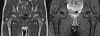

Hip joint의 Bone marrow

1. Yellow / fatty marrow : T1 hyperintense / T2 intermediate

2. Red / hematopoietic marrow : T1 and T2 intermediate because of higher water content

3. Conversion to yellow marrow in apo-/epiphysis of the femur in 1st year